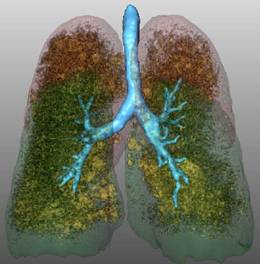

Quantificazione dell'enfisema mediante TC e software MeVisPulmo

Le TC sono state esaminate mediante l'impiego di un software (MeVisPulmo, Bremen) che consente la misurazione totale del volume polmonare, la densità media, i pixel, il "bulla index" e l'analisi sia qualitativa che quantitativa dell'enfisema polmonare. La valutazione prevede la segmentazione delle vie aeree e del polmone. I dati processati vengono storati come immagini DICOM (Digital Imaging and Communications in Medicine). Alla fine della processazione dei dati i valori vengono visualizzati e trascritti in un report. Le regioni lobari vengono indicate con differenti colori nelle sezioni sagittali, coronali e assiali come indicato nella fig. 3-5.

Figura 3. Scansione TC 3D (postero-anteriore). Albero

tracheobronchiale (azzurro), lobi inferiori (verde), lobi superiori

(rosso). I valori di pixels ≤ a -950 HU (giallo), identificano le

zone di enfisema.